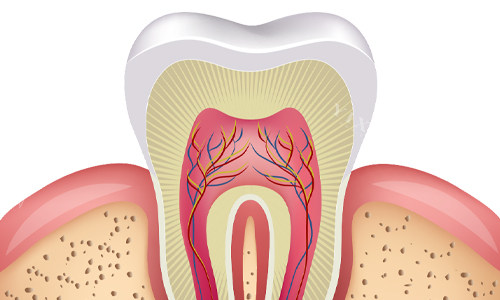

菏泽成武同心口腔拥有一支高素质、正规化的医疗团队。医生团队成员均具备扎实的医学知识和丰富的临床经验,能够正确诊断各类口腔疾病,并制定科学有效的治疗方案。医院还重视与国内外可靠医疗机构的交流与合作,定期引进可靠的口腔技术和设备。

例如,医院引进了智能化口腔影像系统、激光治疗设备、小创口手术器械等,这些设备和技术的运用,不仅提高了口腔诊疗的正确性和效率,同时也减少了患者的不适感和治疗风险。